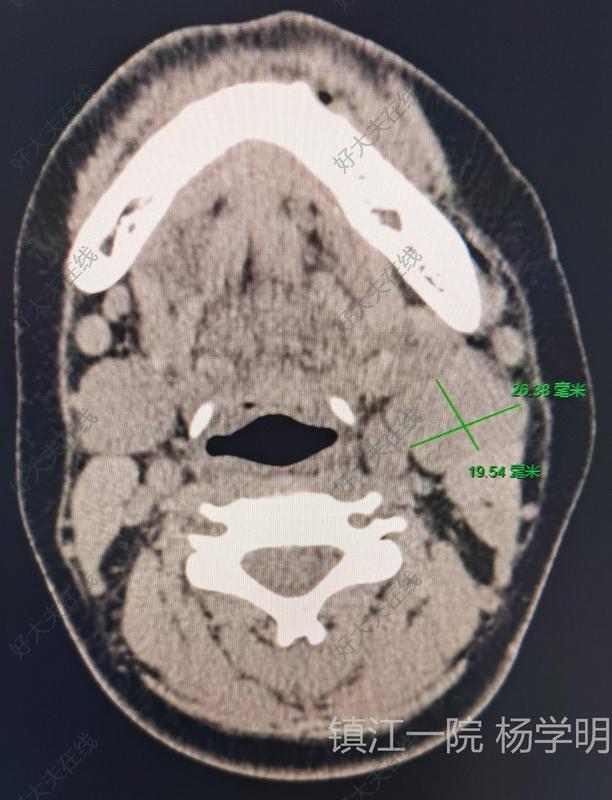

頸部腫塊

鎮(zhèn)江市第一人民醫(yī)院科普號(hào)2023年05月20日265